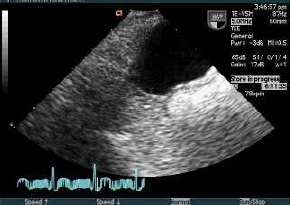

経食道心エコー法(TEE)を積極利用

脳梗塞急性期から、MRIと 頸動脈エコーと経頭蓋のHITS(high intensity thrombotic signals)で

再発作をコントール

頸動脈病変の評価

- 左内頚動脈に低輝度プラークとNASCET法80%の狭窄性病変

- 左内頚動脈の硬化病変を原因とするアテローム血栓性脳梗塞

- HITSを指標として抗血小板薬の治療効果が検証